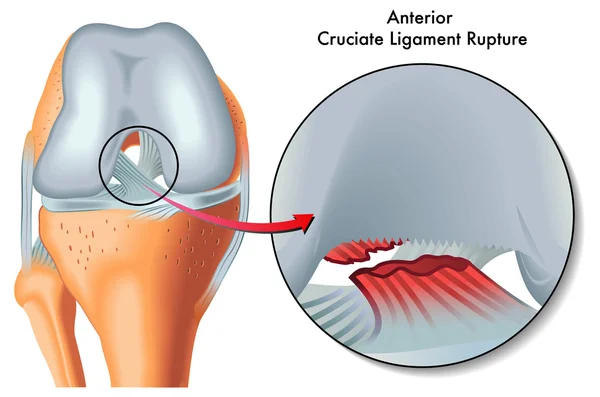

Строение коленного сустава. Повреждения мениска. Разрыв крестообразной связки. Гончаров Е.Н.

Разрыв заднего рога медиального мениска Доктор Мясников Обрезка 01